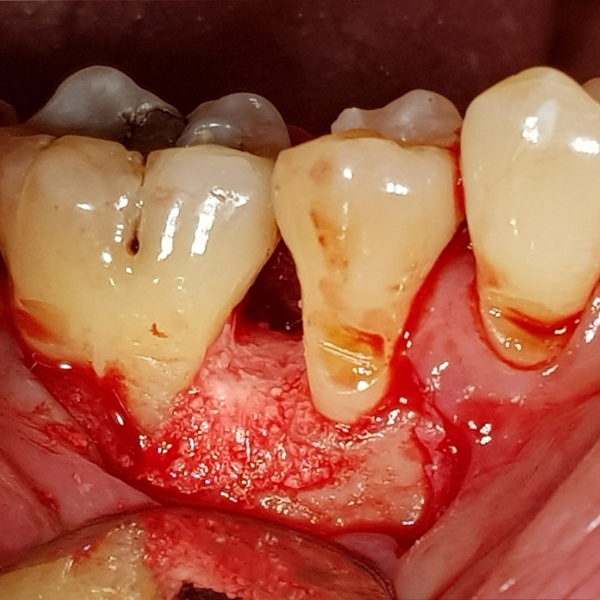

Periodontitis

Two Wall Periodontal Bone Defect

Non-surgical treatment worked to reduce the inflammation but at this site.